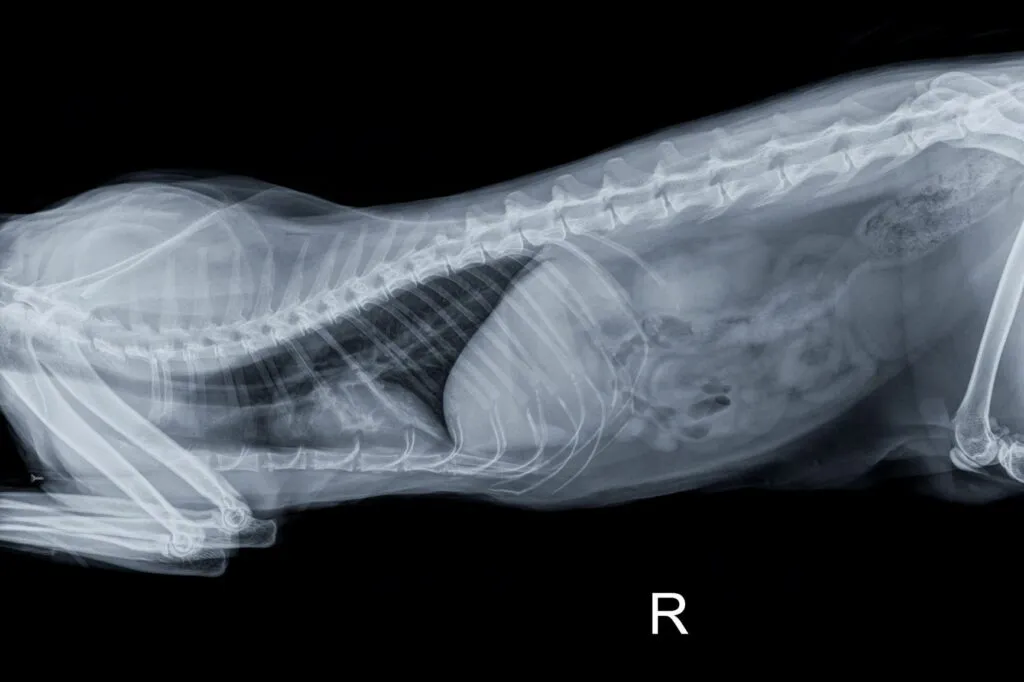

Os ossos dos gatos podem apresentar deformações devido a doenças congénitas ou a uma má alimentação nos primeiros anos de vida. Além disso, os ossos sofrer fraturas em consequência de acidentes com automóveis ou em lutas territoriais particularmente violentas. O veterinário consegue verificar com muita segurança se o gato tem algum osso partido através de um exame por raio X.

© Stefano Garau / stock.adobe.com